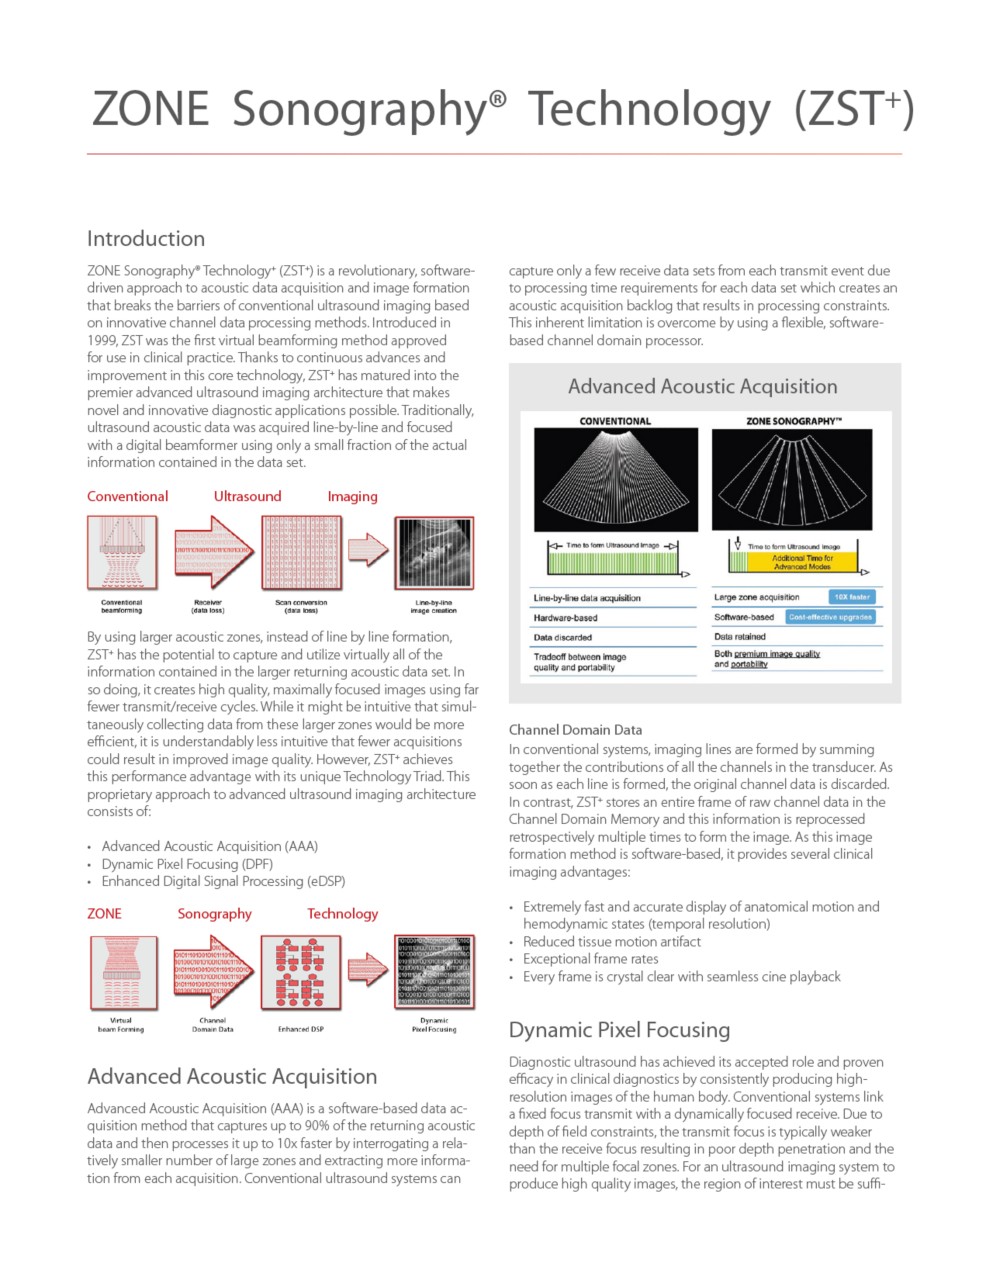

Advanced Acoustic Acquisition

Advanced Acoustic Acquisition (AAA) is a software-based data acquisition method that captures up to 90% of the returning acoustic data and then processes it up to 10x faster by interrogating a relatively smaller number of large zones and extracting more information from each acquisition. Conventional ultrasound systems can capture only a few receive data sets from each transmit event due to processing time requirements for each data set which creates an acoustic acquisition backlog that results in processing constraints. This inherent limitation is overcome by using a flexible, software-based channel domain processor.

Dynamic Pixel Focusing

Conventional ultrasound systems link a fixed focus transmit with a dynamically focused receive. Due to

depth of field constraints, the transmit focus is typically weaker?than the receive focus resulting in poor depth penetration and the?need for multiple focal zones. For an ultrasound imaging system to

produce high quality images, the region of interest must be sufficiently sampled in both the axial and lateral dimensions to prevent several types of imaging artifacts. Dynamic Pixel Focusing permits utilization of the complete channel data set received from multiple, overlapping zones to retrospectively improve the position and focus of each individual data point. Using software algorithms to synthetically focus along every point in the receive beam effectively produces a round-trip beam focused at all depths, eliminating the need for multiple transmit foci. The image is 2-way focused at every point. A typical ZST+ ultrasound image has over 500 range samples, so the net effect is equivalent to a conventional beamformer-based system using 500-600 focal zones.